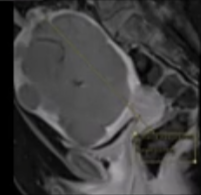

子宫动脉栓塞治疗子宫肌瘤已成为针对此类患者的一种重要且往往能带来重大改变的治疗手段。这些患者因各种严重的症状(如严重的排尿障碍到月经过多)而被转介至各类医疗机构接受治疗。 也有患者因为复发需要接受二次子宫肌瘤动脉栓塞,甚至多次治疗。再治疗率达到了 5%左右。 重要预测因素: 卵巢动脉的供血识别 子宫肌瘤的大小/体积以及子宫的大小/体积 血管供应的范围 复杂的解剖结构 技术方面的问题包括避免痉挛、选择合适的栓塞物等。 发现卵巢动脉供血

成功的栓塞治疗取决于对术前磁共振成像(MRI)结果的仔细分析和标准化处理。重复进行干预治疗最常见的指征是左侧卵巢动脉供血。。 | ||||||||||||||